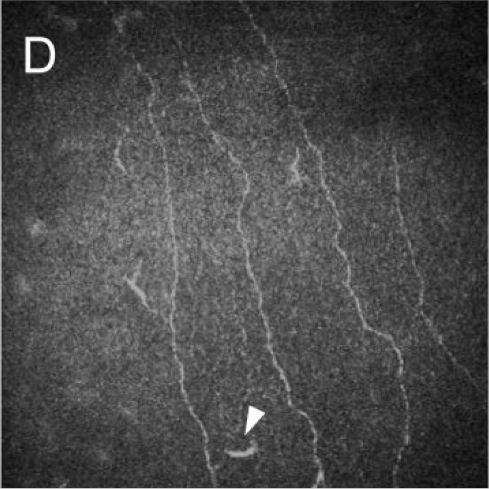

🔬 Corneal Nerve Damage Comparison

Nerve density never recovers to normal levels after LASIK. Compare the healthy, richly innervated cornea before LASIK with the permanently damaged nerve network after surgery.